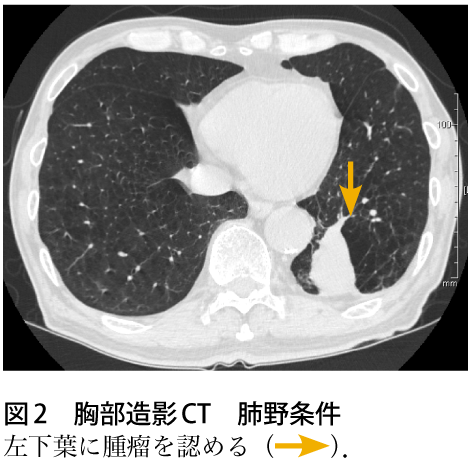

解答 解説 血痰を主訴に来院した70歳代男性 実践 画像診断q A 羊土社 レジデントノート 実践 画像診断q A 羊土社 レジデントノート 羊土社